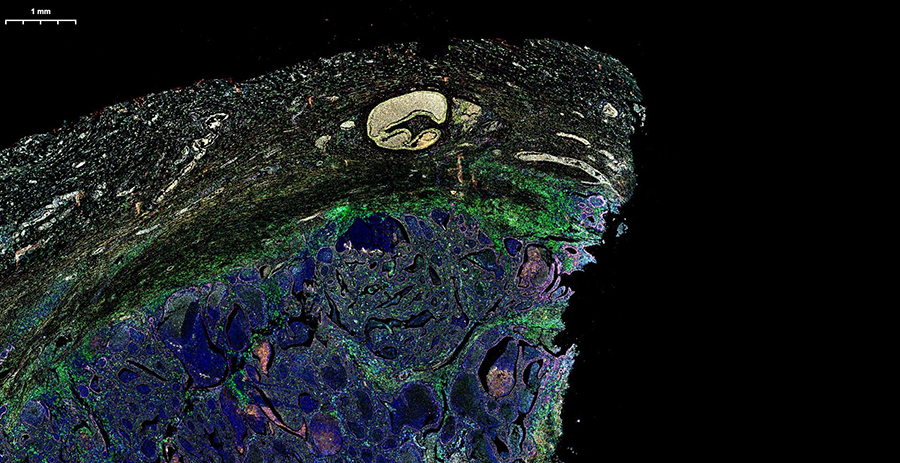

Сможете оценить высочайшее разрешение, скорость обработки (полное стекло за 3-5 минут) и интеллектуальное аналитическое ПО, которое автоматически распознаёт структуры и формирует количественные отчёты с готовыми данными. Можно принести для апробации свои образцы, демонстрируемая конфигурация флуоресцентных каналов (Ex/Em, нм):

Идеальное решение для работы с живыми клетками, флуоресценцией и рутинным мониторингом культур — без затемнённой комнаты и с мгновенным экспортом данных.